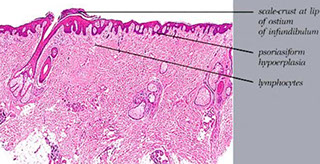

Seborrheic dermatitis

A psoriasiform spongiotic dermatitis occurring in the seborrheic areas including the face, scalp, axilla, and groin, and is assoc c HIV and AIDS, Parkinson disease, epilepsy, neuroleptic drugs, and DM

Micro: netros crusted at edge of hair follicle, irregular epidermal hyperplasia with mild spongiosis, hyperkeratosis, follicular plugging, and mound of scale crust at the shoulder of the follicle